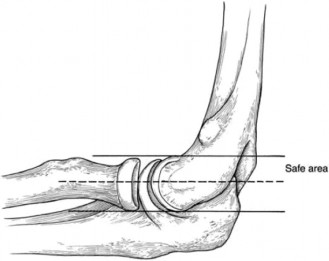

The correct answer is (C). The dorsal scapular artery and nerve travel beneath the rhomboid minor and major muscles approximately 1 to 2 cm medial to the medial scapular border. Portal placement should therefore be located approximately 3 cm medial to the medial scapular border (Fig. 2–80).

Figure 2–80_Reproduced with permission from Warth, RJ, Spiegl UJ, Millet PJ. Scapulothoracic bursitis and snapping scapula syndrome: a critical review of current evidence. _Am J Sports Med 2014 Mar 24. [Epub ahead of print]

Answer A is incorrect because the long thoracic nerve is rarely endangered unless dissection is carried lateral. The suprascapular nerve can be endangered if a portal is placed superior to the scapular spine. The deep branch of the transverse cervical artery becomes the dorsal scapular artery. The spinal accessory nerve travels with the superficial branch of the transverse cervical artery, and its branches are at risk if a portal is placed superior to the scapular spine. Scapulothoracic bursitis is usually managed nonoperatively. Nonoperative treatment includes activity modification, NSAIDs, PT, and corticosteroid injections. If symptoms are recalcitrant to conservative management or associated with an osseous or soft tissue mass, surgical intervention is indicated. Arthroscopic, open, or a combined operative approach can be performed. Arthroscopy is more technically demanding, but it does not require postoperative immobilization because the rhomboids and levator scapulae are not transected and reattached to the scapula after partial scapula resection is performed.